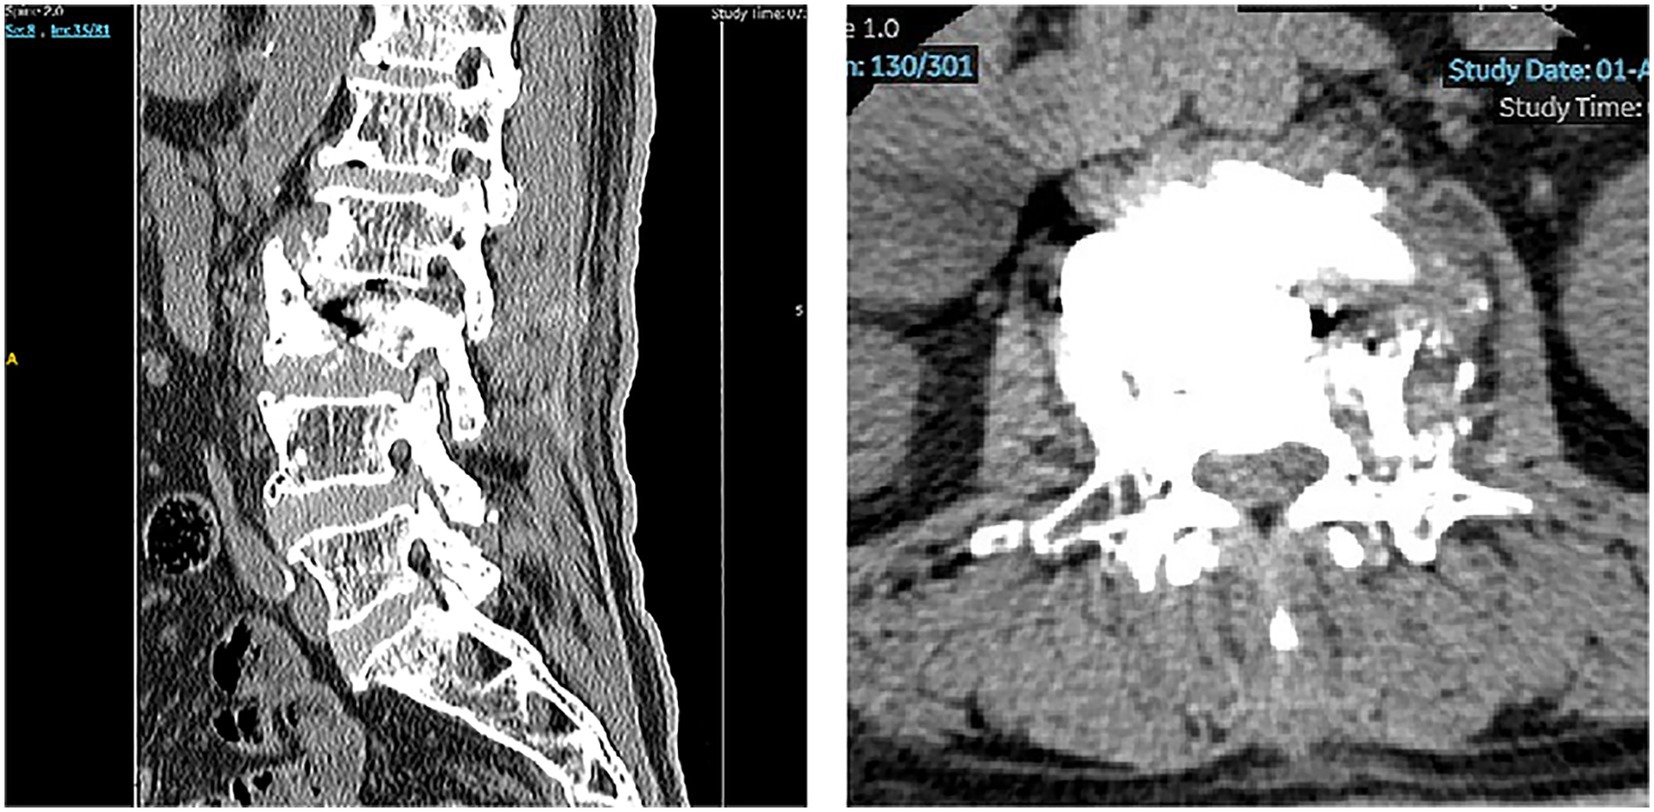

Figure 1

Preoperative radiographs. (A) The preoperative lateral lumbar spine radiographs (DR) revealed an L3 vertebral compression fracture with collapse of the L2/3 intervertebral disk space and a focal kyphotic deformity. (B–D) Preoperative CT of the lumbar spine further confirmed the L3 vertebral body fracture, accompanied by spinal canal stenosis at the L2/3 level.